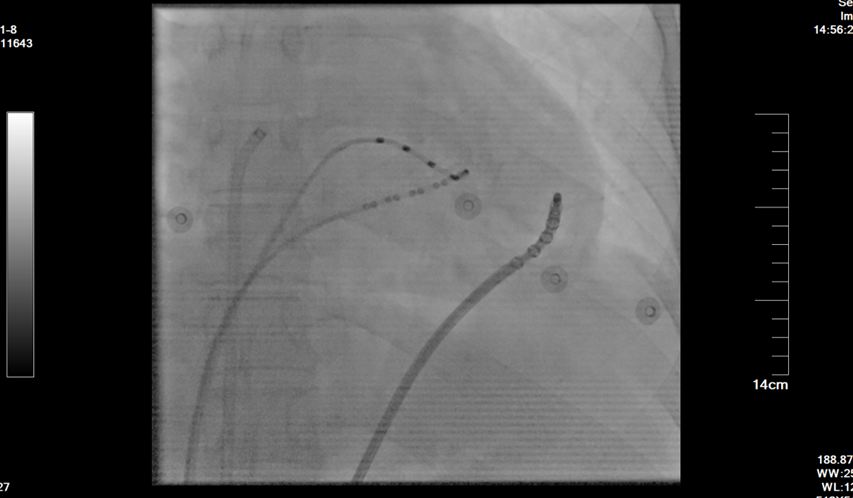

面对这一挑战,在学科带头人周亚峰教授的指导下,陈弹主任医师、王林林教授带领心内科电生理团队共同制定了三维电解剖标测联合心内外膜基质改良的手术方案。手术由王林林教授主导进行,术中通过双侧股静脉入路,精准构建右心室三维模型,标测出右心室下壁广泛低电压区。团队突破性采用干性心包穿刺技术,成功进入心外膜空间,术中采用高功率盐水灌注消融,消融后室速实时终止,并对心内膜、心外膜低电压区进行基质改良。经反复程序刺激验证,室速不再被诱发。术后患者恢复良好,未再出现室速发作,心悸症状完全缓解。相较于传统ICD植入的被动防御,射频消融术通过主动消除心律失常基质,显著降低年轻患者的猝死风险及器械依赖,为其重返正常生活提供可能。